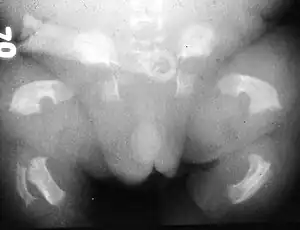

| Radiogram of a baby born with thanatophoric dwarfism | |

Thanatophoric dysplasia is a severe skeletal disorder characterized by a disproportionately small ribcage, extremely short limbs and folds of extra skin on the arms and legs.

Infants with this condition have disproportionately short arms and legs with extra folds of skin. Other signs of the disorder include a narrow chest, small ribs, underdeveloped lungs, and an enlarged head with a large forehead and prominent, wide-spaced eyes. Thanatophoric dysplasia is a lethal skeletal dysplasia divided into two subtypes. Type I is characterized by extreme rhizomelia, bowed long bones, narrow thorax, a relatively large head, normal trunk length and absent cloverleaf skull. The spine shows platyspondyly, the cranium has a short base, and, frequently, the foramen magnum is decreased in size. The forehead is prominent, and hypertelorism and a saddle nose may be present. Hands and feet are normal, but fingers are short. Type II is characterized by short, straight long bones and cloverleaf skull.[1] It presents with typical telephone-handle shaped long bones and H-shaped vertebrae.

Infants with type 1 thanatophoric dysplasia also have curved thigh bones, flattened bones of the spine (platyspondyly) and shortened thoracic ribs. Note: Prenatal ultra-sound images of the ribs sometimes appear asymmetrical when in fact they are not. In certain cases, this has caused a misdiagnosis of osteogenisis imperfecta (OI) type II.